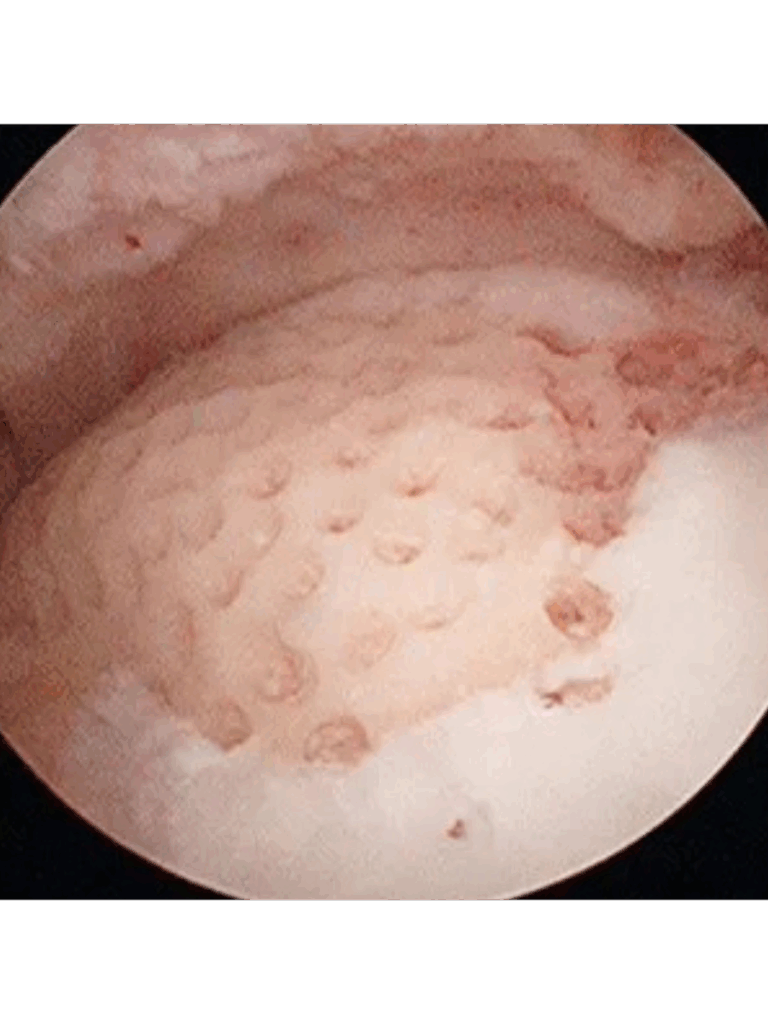

After Stem Cell Treatment

What you’re seeing: The surface is now smooth, shiny, and uniform again — more like a brand-new road.

• The rough patches and holes are filled and replaced by new tissue, which has been stimulated and supported by stem cells.

• Stem cells are the body’s master repair cells. When injected into a damaged joint, they:

• Reduce inflammation and can calm swelling and pain

• Take on whatever form of cell necessary to help heal and regenerate the body, in this case, to regrow cartilage and other supporting tissues when injected into the knee joint

• Improve lubrication inside the joint, so it moves more smoothly -in some cases we will layer viscosupplementation injections to maximize outcomes in this area

• Potentially slow or reverse some of the arthritis and associated degeneration